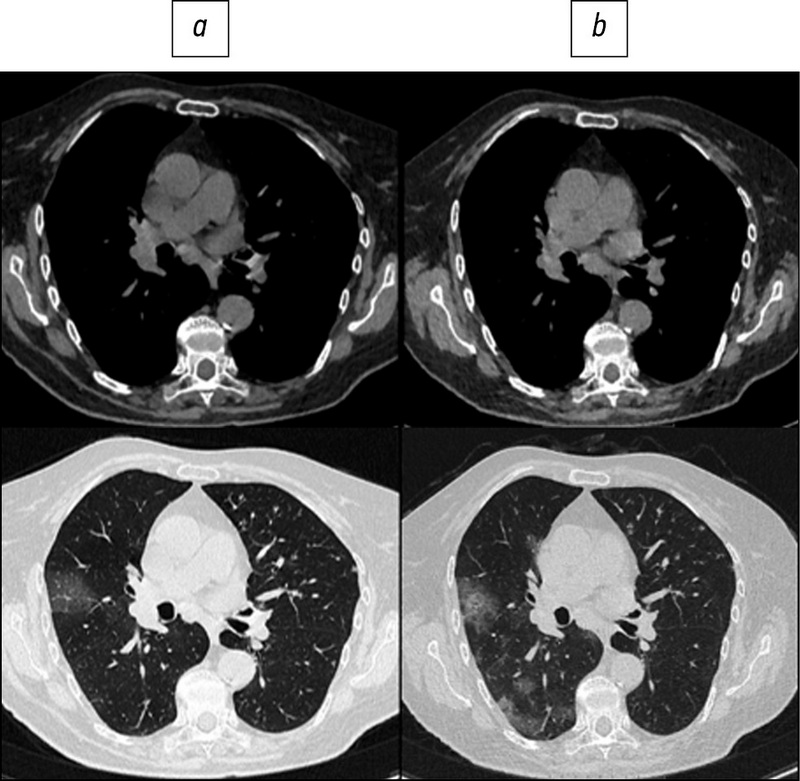

BACKGROUND: Several COVID-19 patients are subjected to multiple imaging examinations during hospitalization, the cumulative effect of which can significantly increase the total dose of radiation received. The effective radiation dose can be reduced by lowering the current and voltage of the X-ray tube, but this reduces image quality. One possible solution is to use adaptive statistical iterative reconstruction technology on the «raw» CT data. Recently, data on the efficacy of low-dose CT (LDCT) in the diagnosis of COVID-19 have appeared in the literature.

AIM: To analyze the quality and diagnostic value of LDCT images of the lungs after applying an iterative processing algorithm and to assess the possibility of reducing the radiation load on the patient when diagnosing COVID-19.

MATERIALS AND METHODS: Patients from the Infectious Diseases Department of the Moscow State University Hospital participated in the prospective study. CT examinations were performed at the time of patient admission and discharge and were repeated as needed during hospitalization. In the first study, a standard CT protocol with a tube voltage of 120 kV and automatic current modulation in the range of 200–400 mA was used; in repeated CT scans, the LDCT protocol was used with reduced tube voltage parameters (100 or 110 kV) and automatic current modulation in the range of 40–120 mA. To assess the diagnostic value of LDCT in comparison with standard CT, a survey was conducted among doctors from the Department of Radiation Diagnostics at Moscow State University Hospital. The questionnaire included a comparison of the two methods for identifying the following pathological processes: «ground-glass» opacities, compaction of the lung tissue with reticular changes, areas of lung tissue consolidation, and lymphadenopathy.

RESULTS: The study included 151 patients. The average age was 58±14.2 years, with men accounting for 53.6% of the population. During LDCT the radiation load was reduced by 2.96 times on average, CTDI by 2.6 times, DLP by 3.1 times, the current on the tube by 1.83 times, and the voltage on the tube by 1.2 times. The results indicate that the effectiveness of detecting the main signs of viral pneumonia and assessing the dynamics of the patient’s condition does not differ significantly from CT performed according to the standard protocol.

CONCLUSIONS: The results of a comparison of standard and low-dose CT show that there is no significant loss of diagnostic information and image quality as the radiation load is reduced. Thus, chest LDCT can be used to successfully diagnose COVID-19 in routine practice.